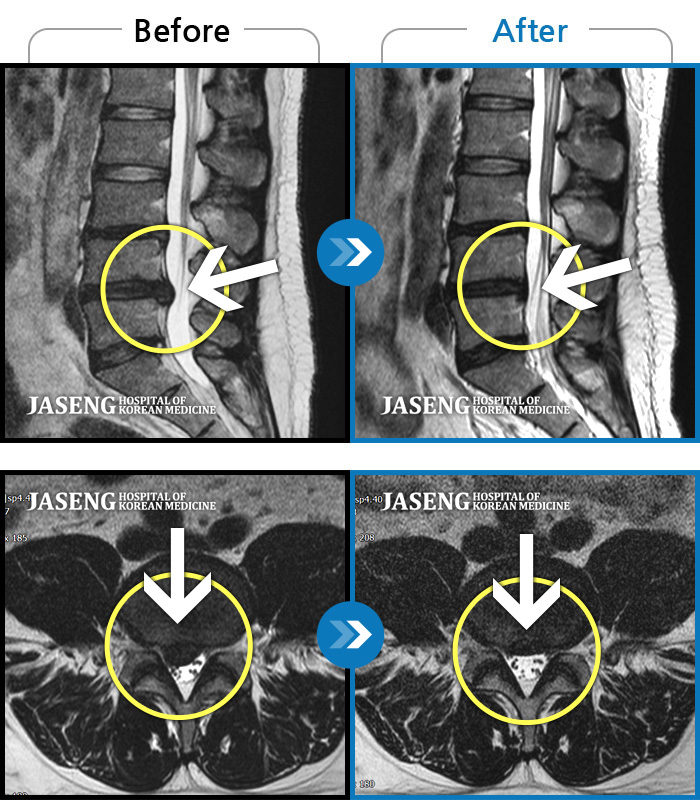

허리디스크

인천 · 강아현 원장

물건을 들다 삐끗한 후 발생한 허리 통증 및 하지 방사통, 하지 감각 저하 및 근력 저하 발생

촬영시기

2025.03.04 ~ 2025.09.10

2025.09.22